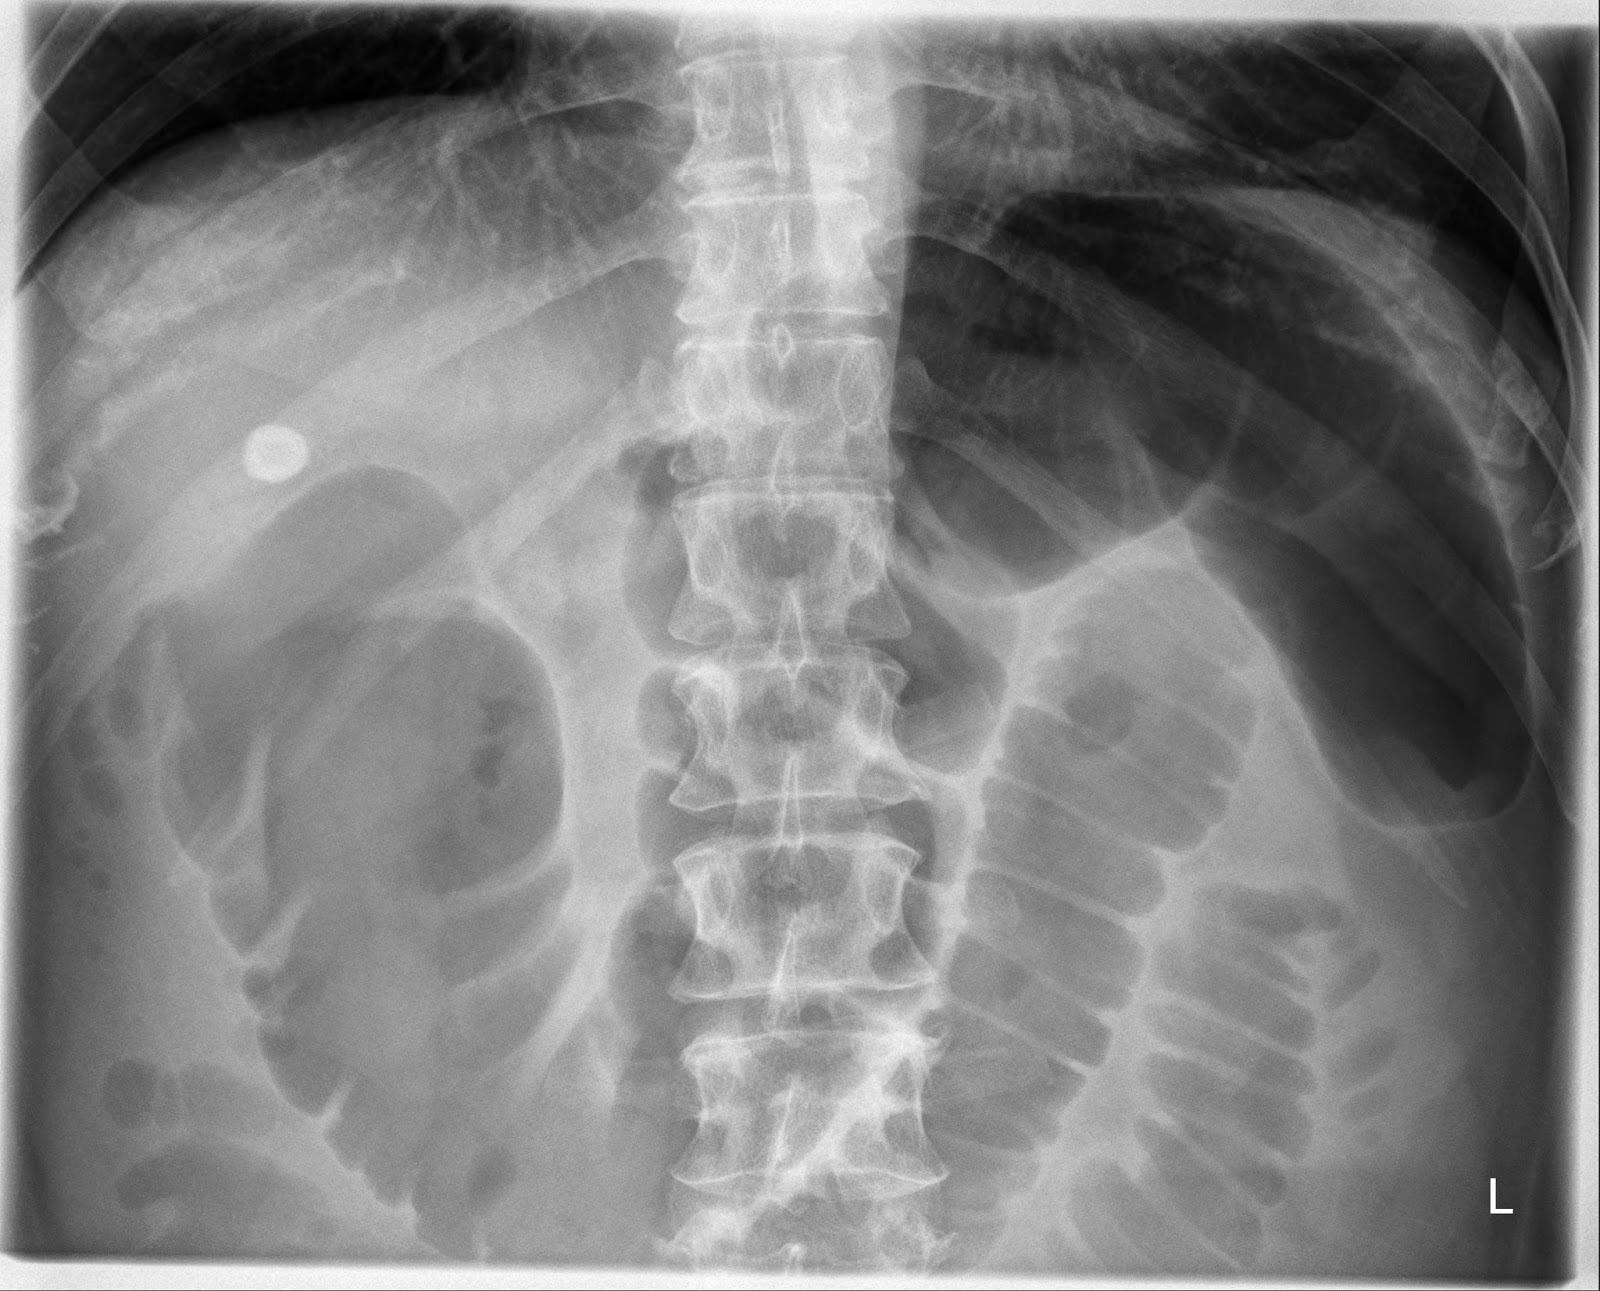

Sentinel loop sign and colon cutoff sign in a similar plain abdominal Sentinel Loop On X Ray A sentinel loop is a radiographic finding of a. A localized ileus, also called sentinel loops, is a functional type of obstruction caused by irritation of a loop or loops of bowel. It may indicate pancreatitis, appendicitis, or other. the sentinel loop sign is a radiographic finding of localized ileus on supine abdominal radiographs, indicating. a sentinel loop. Sentinel Loop On X Ray.

Sentinel loop sign and colon cutoff sign in a similar plain abdominal Sentinel Loop On X Ray A sentinel loop is a radiographic finding of a. See the features of dilated loops of gas. learn how to identify and categorize abnormal bowel gas patterns on radiographs and ct scans. A localized ileus, also called sentinel loops, is a functional type of obstruction caused by irritation of a loop or loops of bowel. It is the dilation. Sentinel Loop On X Ray.

Sentinel loop sign and colon cutoff sign in a similar plain abdominal Sentinel Loop On X Ray the sentinel loop sign is a radiographic finding of localized ileus on supine abdominal radiographs, indicating. It may indicate pancreatitis, appendicitis, or other. A localized ileus, also called sentinel loops, is a functional type of obstruction caused by irritation of a loop or loops of bowel. See the features of dilated loops of gas. a sentinel loop is. Sentinel Loop On X Ray.